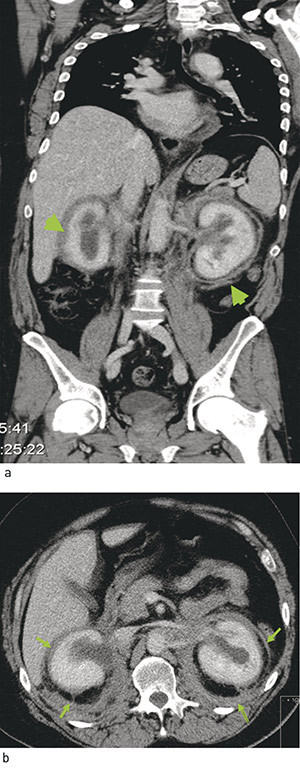

CT thorax og abdomen viste bløtdelsoppfylling langs aorta i flere nivåer, og i nedre del omkranset vevsfortykkelsen hele aorta. Fra nivå med nedre nyrepol og til bifurkaturen var det utbredelse som ved retroperitoneal fibrose med fortykket perirenale fascie. Innenfor perirenalt fettvev var også begge nyrekapsler fortykket med forandringer vel forenlig med «hairy kidneys» (fig 2). Begge nyrebekkener var dilatert, uten utvidelse av ureter.

Et karakteristisk funn ved Erdheim-Chesters sykdom er infiltrasjon av perirenalt vev, som på CT kan ses som «hairy kidneys». Dette kan påvises hos opptil 68  % av pasientene (5), og ble også funnet hos vår pasient.

Ved hjerteaffeksjon affiseres perikard hyppig, det kan føre til komplikasjoner som hjertetamponade (10). Ved aortaaffeksjon ses oftest sirkumferensiell infiltrasjon rundt torakal- og/eller abdominalaorta. Dette har fått betegnelsen «coated aorta» (5) og ble funnet hos vår pasient. Infiltrasjonen rundt aorta ved Erdheim-Chesters sykdom rammer også den bakre del av aorta, mens ved idiopatisk retroperiotoneal fibrose, som vi først mistenkte at pasienten hadde, affiseres som regel bare den fremre og laterale del av aorta. Infiltrasjonen rundt aorta kan spre seg til større avgangskar og medføre stenoser.